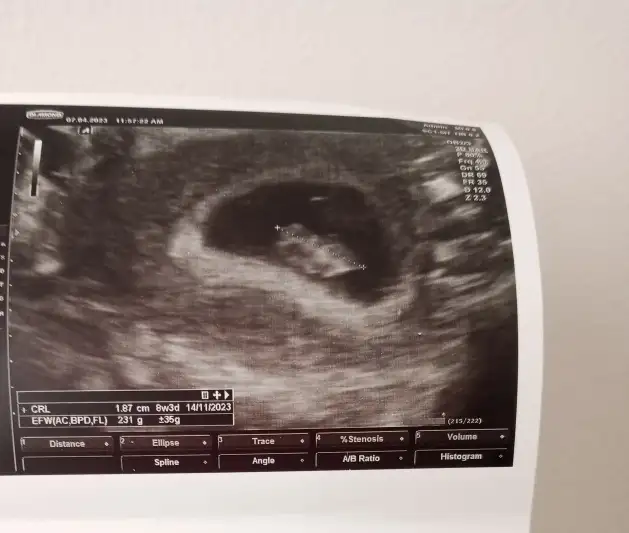

MaşallahMerhaba kizlarr az önce hastaneden geldim çok şükür kese gorunfu bebek göründü kalp atımı var ama dinletmedi doktorum küçük olduğu için 2 hafta sonraya randevu verdi cokk mutluyum şuanbuda ultrason fotimizzz burdan tahmin yapan teyzoslar vardı bana da bakabilir mii neyimiz olacak acaba

Merhaba kizlarr az önce hastaneden geldim çok şükür kese gorunfu bebek göründü kalp atımı var ama dinletmedi doktorum küçük olduğu için 2 hafta sonraya randevu verdi cokk mutluyum şuanbuda ultrason fotimizzz burdan tahmin yapan teyzoslar vardı bana da bakabilir mii neyimiz olacak acaba